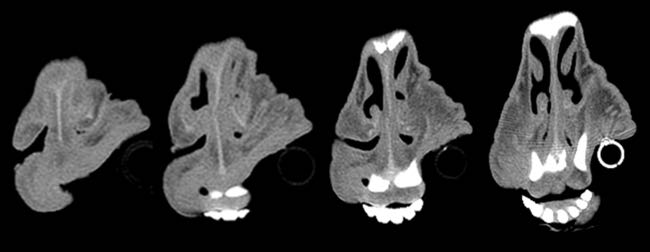

Given the clinical findings and prior experience with upper airway disease, ancillary tests were performed. Thermography did not identify consistent focal increases in temperature across the six animals, making common differentials such as chronic proliferative rhinitis (CPR) or enzootic nasal adenocarcinoma (ENA) less likely. Oestrosis had also been ruled out, as previous treatments targeting this condition failed to result in clinical improvement in the affected animals. Computed tomography (CT) of the head revealed increased soft tissue in the rostral nasal cavity, producing variable obstruction of the nasal meatuses in all sheep. On transverse CT images, soft-tissue thickening causing luminal narrowing was confined to the most rostral nasal cavity and decreased progressively on more caudal slices, where the nasal airway regained a wider lumen (Figure 3). This localisation of obstruction at the alar fold level explained the inspiratory dyspnoea and snoring.